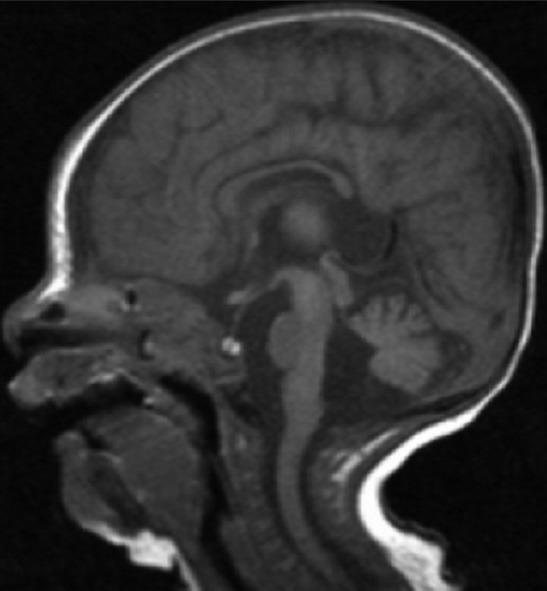

We report a case of 4 weeks old girl with a de novo interstitial deletion of the short arm of chromosome 3 (p13-p21) and clinical findings typical of proximal 3p deletion together with heart defects, choanal atresia, ear anomalies, central nervous system anomalies, renal anomalies and associated Joubert's syndrome (JS). Family history is unremarkable and parenteral chromosomes were normal. The clinical manifestations of the patient are compared with those of 11 patients previously described with a proximal 3p deletion. The additional JS features associated with this syndrome were described. This is the first case report in English literature describing 3p deletion associated with additional JS features.